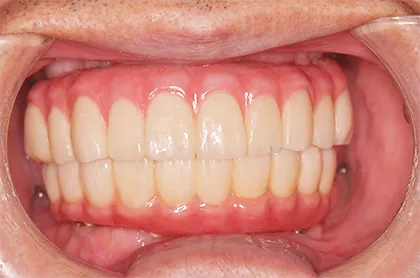

- BEFORE

| 年代・性別 | 70代・男性 |

|---|---|

| 主訴 | 今使っている入れ歯が合わず、嚙むと痛い |

| 治療部位 | 15~26、36、45 |

| 治療内容 | 上下顎インプラント埋入術(上顎5本、下顎2本)を、2回に分けて実施。26部はソケットリフトを適用し、2回法で実施。他部位は1回法。 |

| 金額(税込) | 29,000,000円(税込) |

| 治療期間 | 7カ月(インプラント埋入から上部構造装着まで) 12年経過例(2024年3月時点) |

| リスクと副作用 | 手術部位の腫脹、疼痛 マスダ歯科のインプラント詳細はこちら |